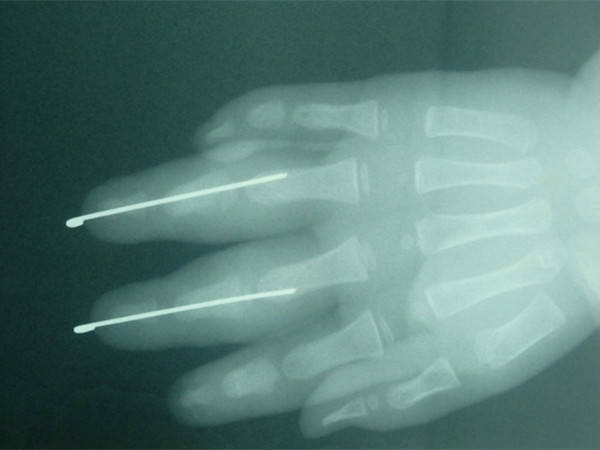

患儿2岁,三角带夹伤致右手中、环指中节基底以远离断。